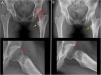

En los casos de CFA, la capsulotomía fue interportal. En los casos de displasia limítrofe, la capsulotomía artroscópica fue mínima, respetándose el ligamento iliofemoral y sin conectar los 2 portales25. El tendón del psoas no se liberó en ningún caso y tampoco se efectuó resección ósea acetabular25. No se efectuó capsulorrafia en ningún caso de displasia, considerando que se hizo una capsulotomía puntiforme. Un 83% de los casos de displasia presentó una lesión de CAM asociada, en los que se resecó el mismo mediante control radioscópico de la misma forma que en los casos del grupo CFA (fig. 1).

Paciente de sexo femenino de 32años. A) Radiografías anteroposterior y perfil preoperatorias; LCEA=25°; ángulo de Tönnis=10°; ángulo alfa=80°. Flecha amarilla: coxa valga y extrarrotación; flecha continua roja: deformidad tipo CAM; flecha roja punteada: osteofito en anillo.

B) Radiografías anteroposterior y perfil postoperatorias inmediatas; LCEA y Tönnis sin modificación; flecha roja continua: corrección de la deformidad de CAM luego de la osteocondroplastia artroscópica.